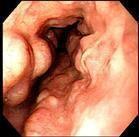

食管穿透性損傷

• 食管穿透性損傷

628健康網為您分享有關食管穿透性損傷的癥狀,食管穿透性損傷的治療方法,食管穿透性損傷的預防知識,食管穿透性損傷的癥狀...